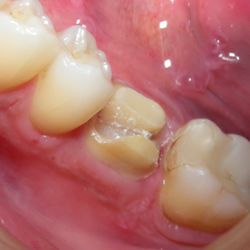

Ο προγόμφιος της φωτογραφίας υπέστη κάταγμα του παρειακού φύματος λόγω εκτεταμένης παλιάς έμφραξης αμαλγάματος.

Προκειμένου να αποφευχθεί ο τροχισμός του δοντιού για τοποθέτηση στεφάνης, διαδικασία που μπορεί να οδηγούσε σε νέκρωση του δοντιού, αποφασίστηκε η αφαίρεση της παλιάς έμφραξης αμαλγάματος και η αποκατάσταση του δοντιού με ένα επένθετο εργαστηριακής σύνθετης ρητίνης.

Ο εκτροχισμός που απαιτήθηκε για αυτή την διαδικασία ήταν ελάχιστος, έτσι το δόντι διατηρήθηκε ζωντανό χωρίς προβλήματα.